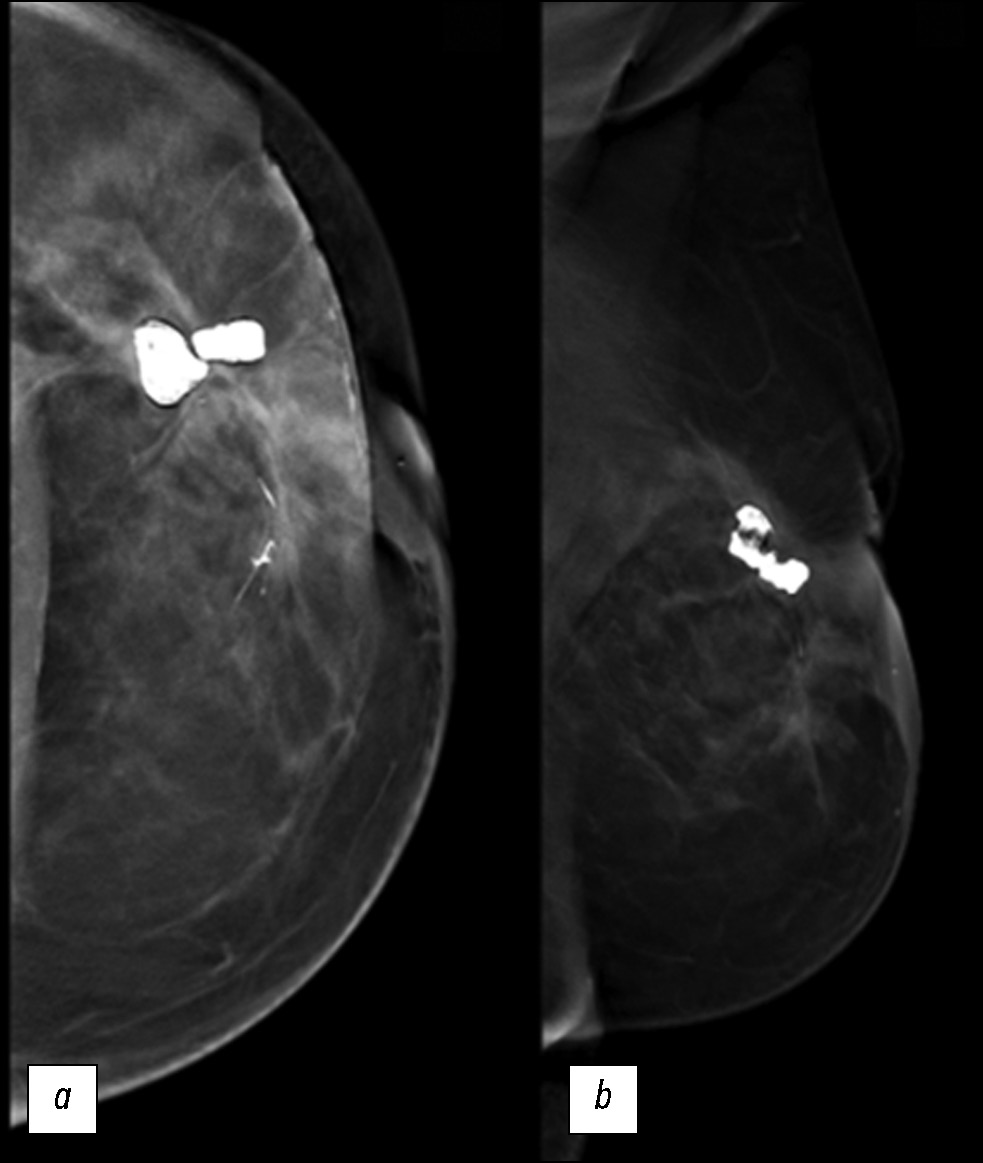

本文描述了一个罕见的继发性乳腺血管肉瘤病例,患者是一名72岁的女性,患者是一名有乳腺癌病史的 72 岁女性。曾患乳腺癌。患者因左乳房外上象限无痛性可触及硬块来我院就诊,接受了全面的诊断检查,包括乳腺科、病理科和肿瘤科的会诊。在乳房造影、超声检查和磁共振成像等仪器诊断方法的帮助下,成功评估肿瘤的扩散程度、淋巴结损伤情况,以及是否存在远处转移。 组织活检结果证实了诊断。本文分析这一罕见病例的主要目的是教育性的,包括描述该疾病的临床表现和复杂诊断,以及讨论鉴别诊断和治疗策略。继发性乳腺血管肉瘤是一种罕见的侵袭性肿瘤,了解其独特之处对于做出正确的临床决策和改善患者的预后至关重要。由于发现较晚、硬块远处转移的风险增加以及治疗方案有限,该肿瘤的预后较差。在这种情况下,需要密切监测、采取积极的治疗策略和姑息治疗。